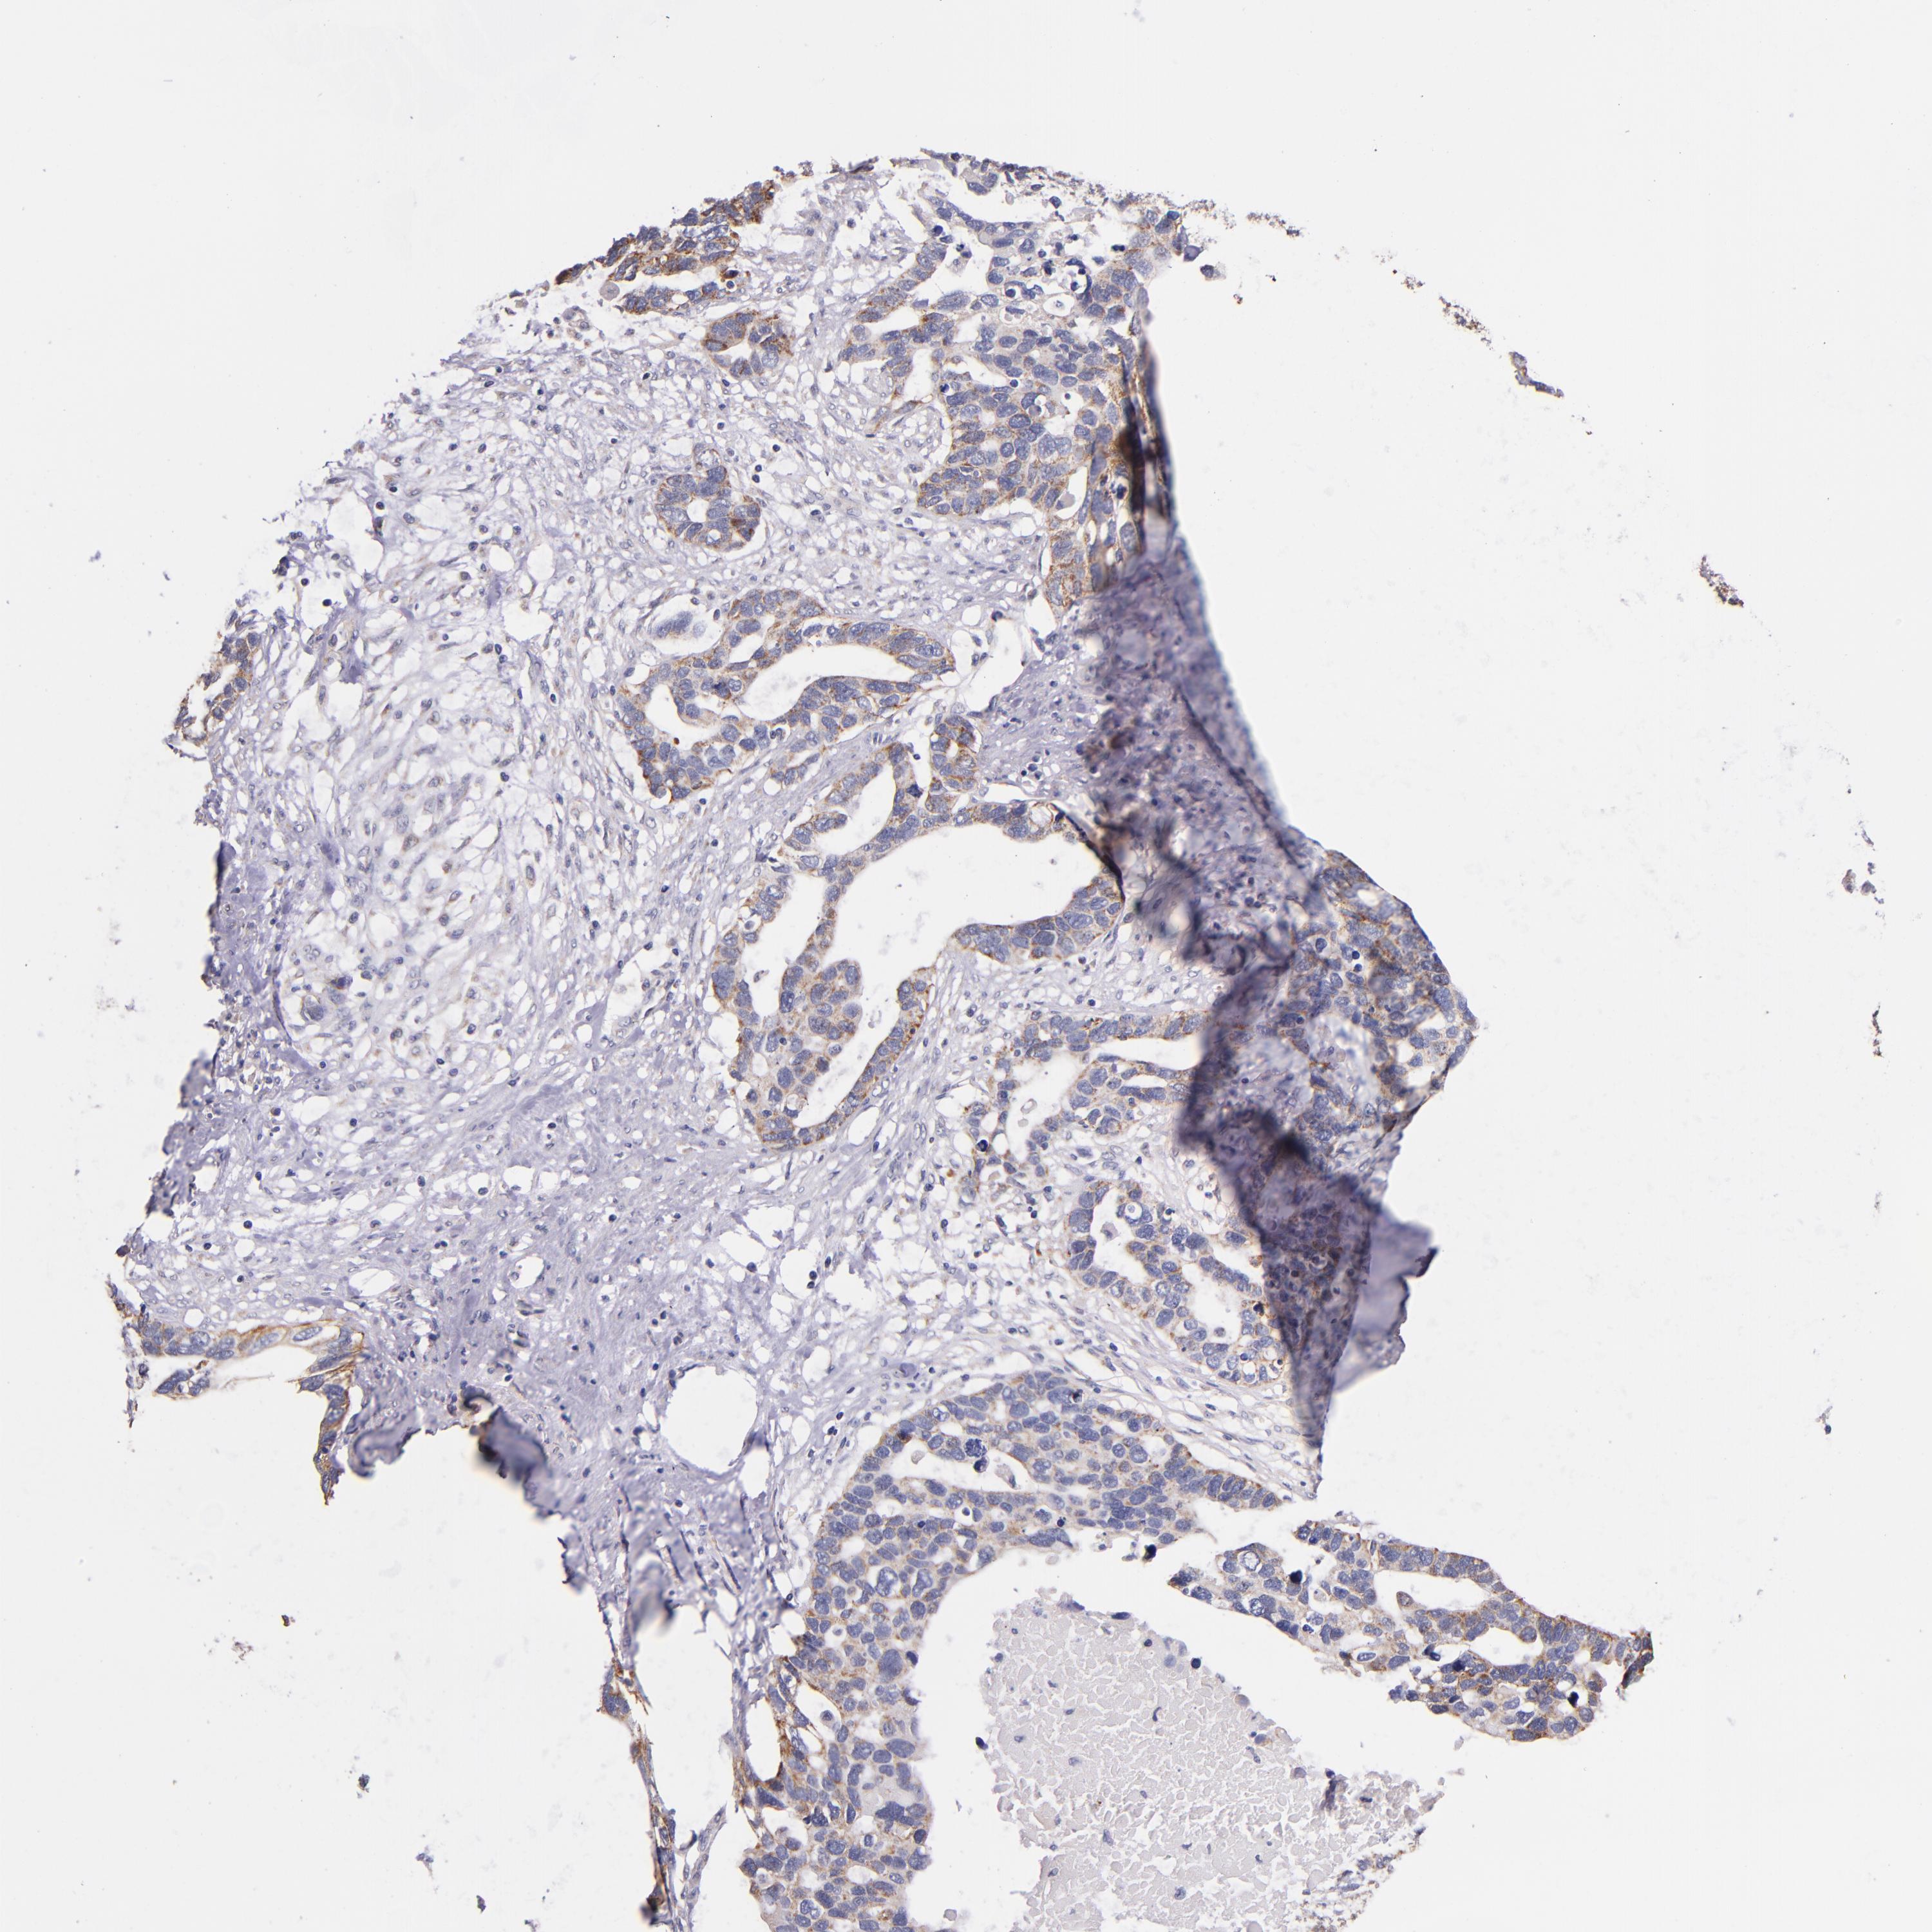

OVARIAN CANCER - Protein expressioni

A mouse-over function shows sample information and annotation data. Click on an image to view it in a full screen mode. Samples can be filtered based on level of antibody staining by selecting one or several of the following categories: high, medium, low and not detected. The assay and annotation is described here.

Note that samples used for immunohistochemistry by the Human Protein Atlas do not correspond to samples in the TCGA dataset.

Antibody stainingi

Antibody staining in the annotated cell types in the current human tissue is reported as not detected, low, medium, or high, based on conventional immunohistochemistry profiling in selected tissues. This score is based on the combination of the staining intensity and fraction of stained cells.

Each image is clickable and will lead to virtual microscopy that enables deeper exploration of all samples and also displays staining intensity scores, fraction scores and subcellular localization as well as patient and tissue information for each sample.

Antibody HPA001844

Cystadenocarcinoma, serous, NOS